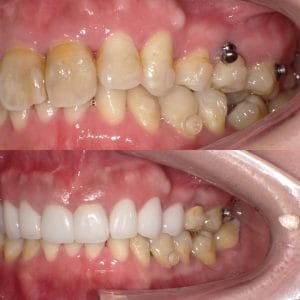

Case021 – インプラント

「ずっと放置してしまっていた。今回はちゃんとしっかり治したい」ということで、強い意志をもって来院してくださった患者様の症例です。

インプラント治療、セラミック治療、歯周病治療により、審美性と機能、咬みあわせの再建を行いました。

患者様は咬みあわせの確立により、食事もしやすく、普段の顎関節の状況も良くなり、機能の回復にも満足してくださり、また審美性も喜んでくださいました。

放置期間が長くだいぶ骨が溶けてしまっていたので、前歯部のインプラントは骨の再生療法などが必要だったりしましたが、患者様が治療への前向きな姿勢をだしてくださっていましたので期間も最短で終わりました。

一度放置してしまうと、億劫になってしまってなかなか行動に移すのは難しいと思いますが、少しでも早く治してあげた方が毎日の食事も楽になりますし、お顔の見栄えもお顔の骨格の歪みも改善します。

担当 理事長 佐藤 悠野